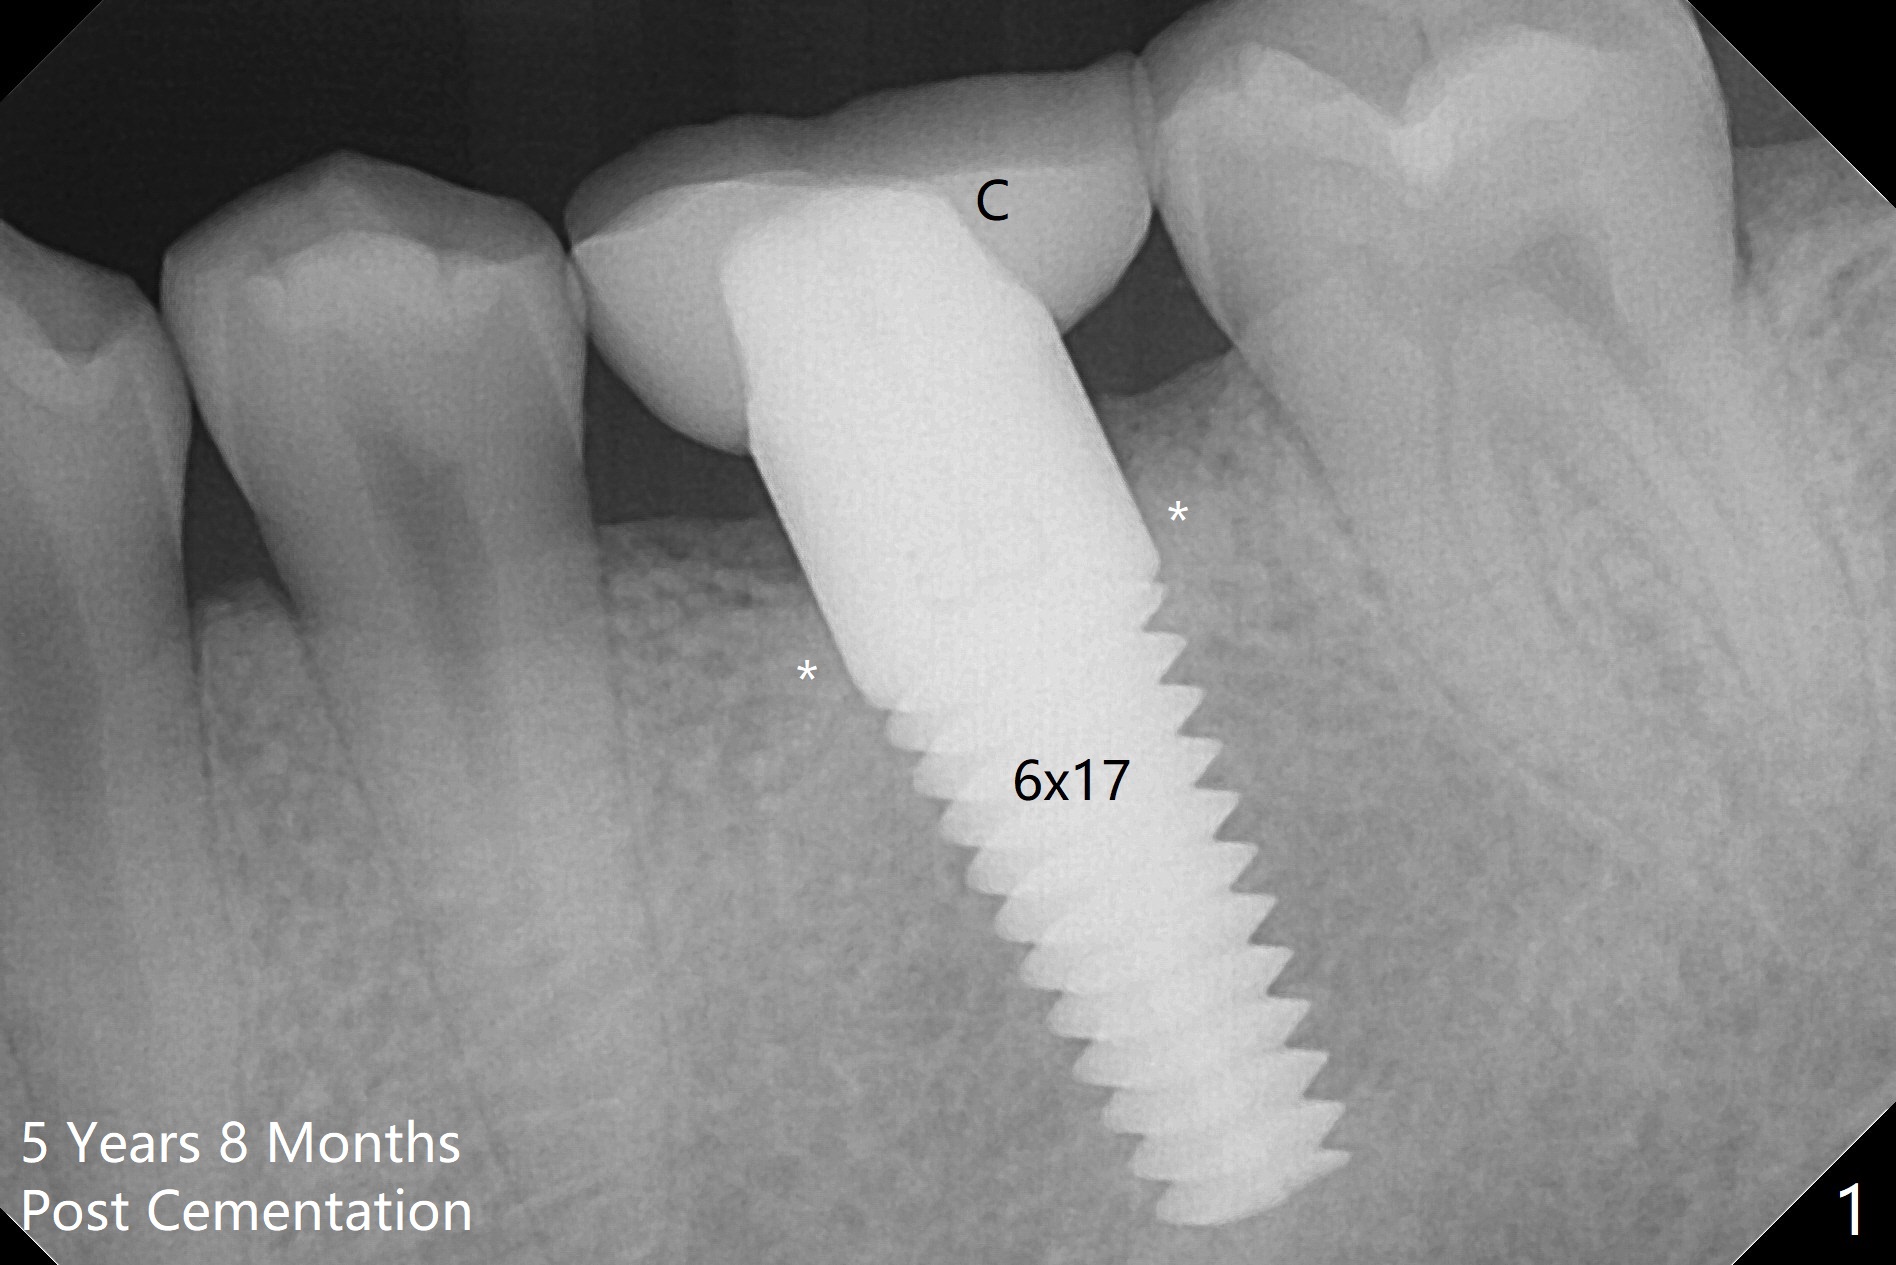

A 29-year-old man returns for follow up 5 years 8 months post cementation of the crown at #19 (Fig.1; 2 (bitewing)). The bone density around the coronal end of the 6x17 mm tissue-level implant (8 months post extraction without socket preservation) is high (*). Why is the implant crown (C) short?